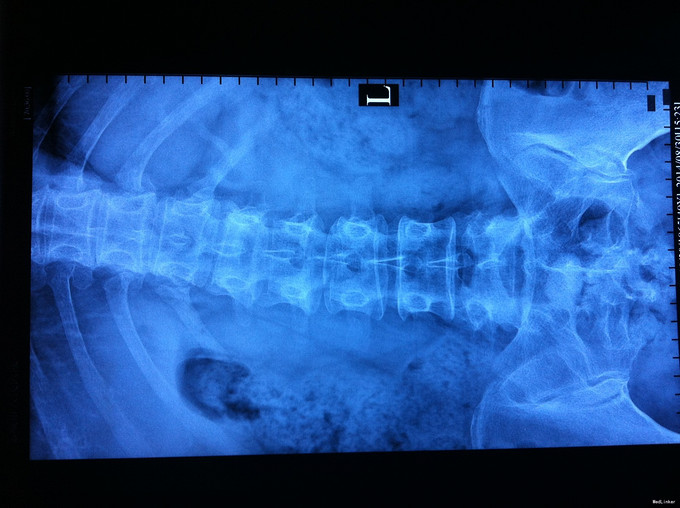

专科查体无下肢神经损伤表现:腰部叩痛,腰部活动受限,双下肢感觉无异常,双下肢肌力4-5级,双侧膝腱反射++,跟腱反射+,双侧巴氏征阴性, X-ray:腰1椎体骨折,累及前中柱,腰3椎体骨折。CT:腰1、3椎体骨折,累及中柱。MR:腰1、3骨折,新鲜骨折。影像学检查提示腰1椎体骨折较重。

诊断:腰椎骨折 腰1、3椎体 处理:1、完善相关辅助检查,明确诊断,有无手术指证; 2、完善手术评估,有无手术禁忌,手术风险及并发症; 3、在全麻下行腰1椎体后路撑开复位内固定术,腰3椎体压缩较轻,可卧床保守治疗。